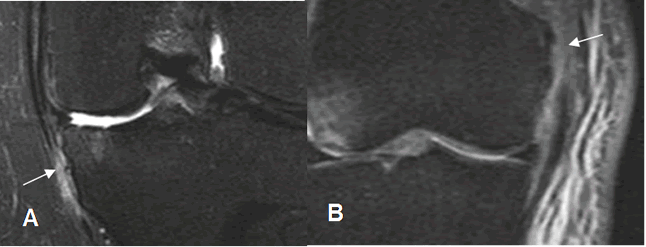

Fig 120. Ruptura del LCM.

A y B: RM coronal en STIR. Ruptura del LCM en la inserción tibia (A) y en el origen

femoral. (B).